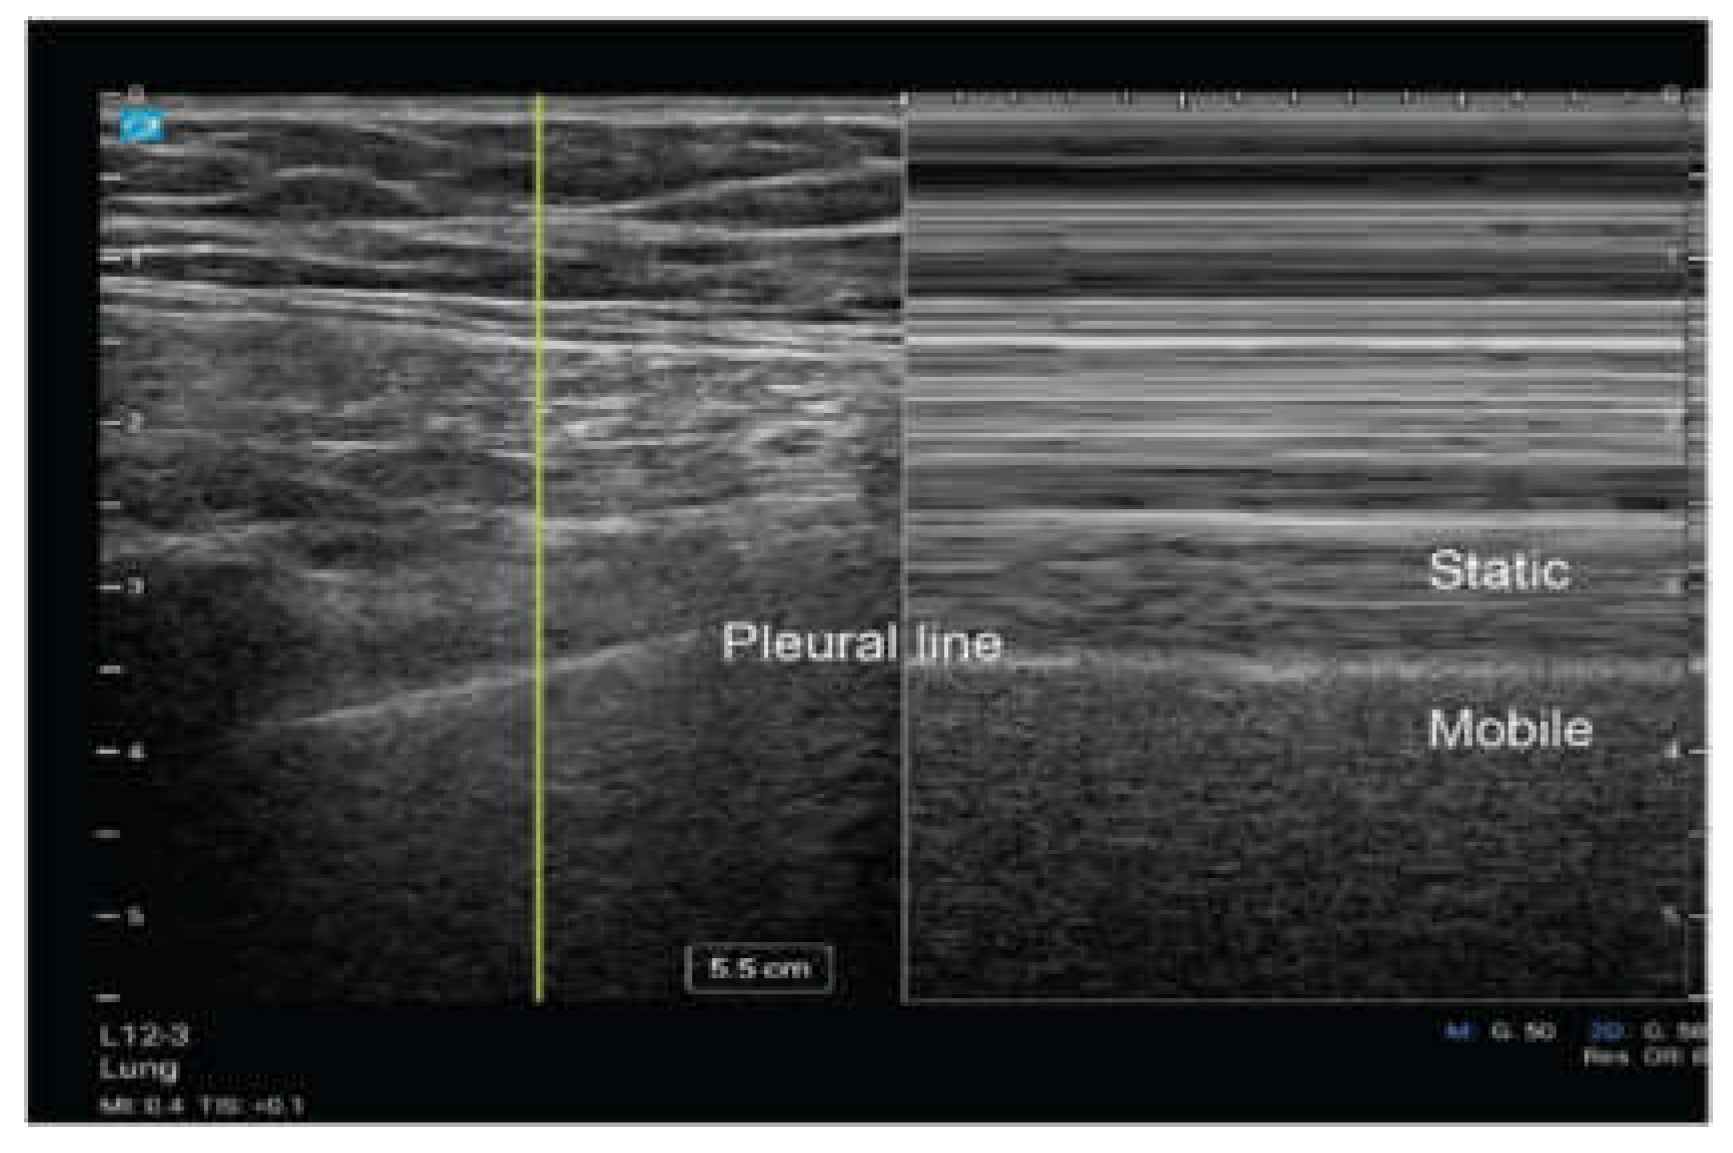

Lung Sliding

During the respiratory cycle, the visceral and parietal pleura move relative to each other. Utilizing ultrasound, this dynamic movement can be visualized as a shimmering effect along the pleural line referred to as “lung sliding.” This movement can be seen with two dimensional (2D) ultrasound (Video 1) and motion (M) mode (Figure 4) [16]. When using M mode, it is classically described as the pattern of “sandy beach” with the proximal subcutaneous tissue representing water, and the movement of the lung parenchyma representing a beach [16]. The presence of lung sliding suggests that the evaluated region is being actively ventilated with the lung parenchyma reaching the pleural line, and it significantly reduces the likelihood of pneumothorax at thatsite [10].

Figure 4. M mode demonstrating lung sliding in 2-dimensional (2D) ultrasound and Motion mode (M-mode).